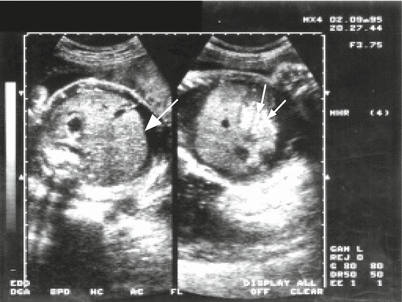

Fig. 15.9

Cross-section of the fetal cephalic pole with periventricular calcifications (arrows) in the context of a fetal infection of cytomegalovirus, noting the presence of lateral ventricle dilation